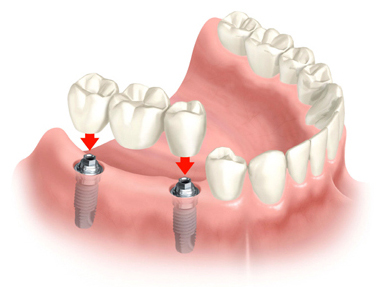

Implants can also be used as support as part of an implant bridge.

This is an alternative to partial dentures, and has several advantages. First, there is no adjustment period to acclimatize the patient who, once the work is done, the patient only feels teeth, not metal supports intruding into the mouth. Second, this slows the bone loss occasioned by missing teeth. Third, there is no discomfort or difficulty in eating. And, best of all, of course, they don't have to be taken out.